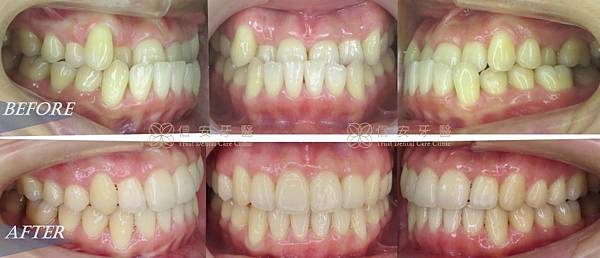

▲小靜只花一年時間,就把原本異常的咬合關係矯正到正確位置上,現在講話再也不「漏風」了!

▲側面錯咬的情形也已經改善

▲小靜一顆牙都沒有拔!牙齒卻依舊排列的相當理想整齊

▲連小靜自己都覺得不可思議,不用動刀、不用拔牙、一年的時間就可以有如此巨大的改變,輕鬆又快速的療程讓她不禁大為慶幸:自己找對醫生了!

▲對比矯正前,小靜現在的笑容變得比以前更自然漂亮並且充滿自信!